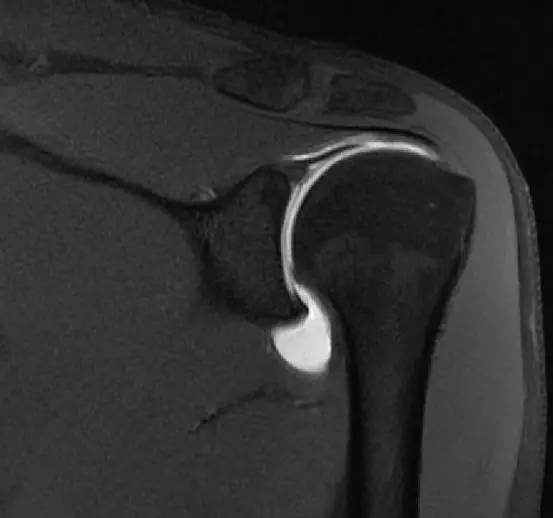

这是一个肩关节造影的磁共振片子,包括肩胛下肌,冈下肌,冈上肌

这张片子是肩胛下肌,上盂唇,冈上肌,冈下肌

到这个层面,可以看到肩胛下肌建,冈上肌腱,冈下肌建